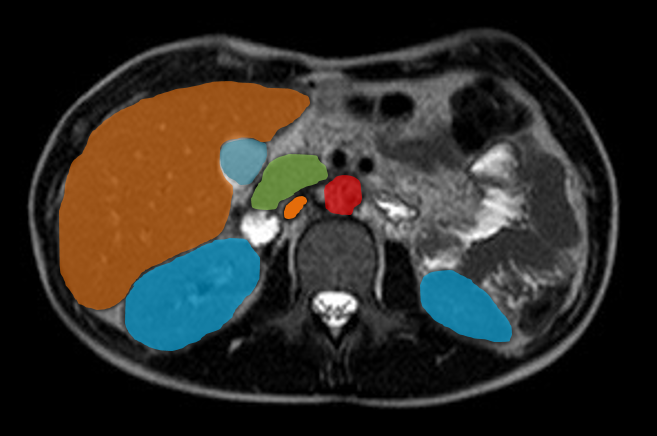

In der interventionellen Radiologie beschränkt sich die Tätigkeit des Radiologen nicht allein auf die bildgebende Diagnostik. Vielmehr übernimmt er eigenständig minimalinvasive Eingriffe und trägt dabei die Verantwortung für die prä-, peri- und postoperative Versorgung der Patient: innen.